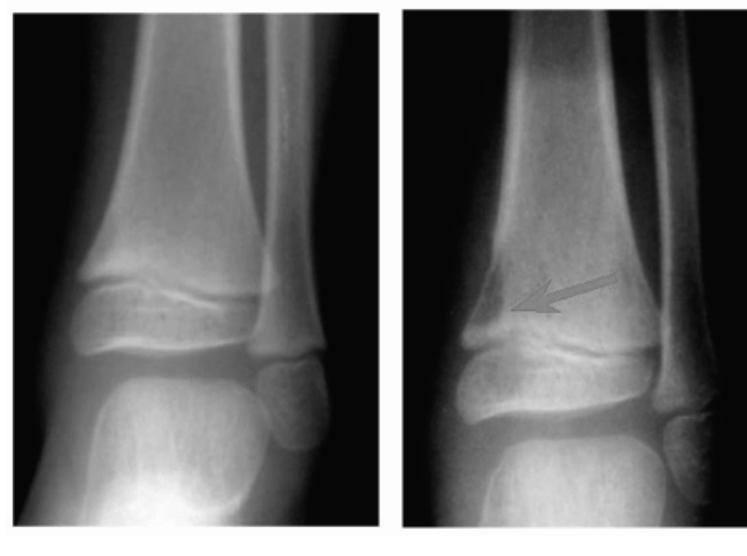

| Entry Points | Proximal Tibial Site: - Insertion: Laterally at a point 2cm distal and 2cm posterior (lateral) to the Tibial tuberosity. - Exit: Medially. - Avoids: Injury to the common peroneal nerve. Distal Femoral Site: - Insertion: Medially at level of upper patella in-line with mid-femur. - Exit: Laterally. - Avoids: Popliteal vascular damage and intra-articular injury. | Proximal Tibial Site: Distal Femoral Site: ![]() |